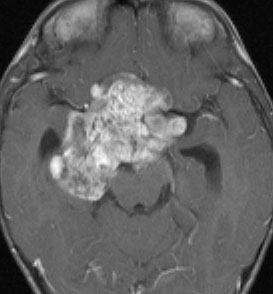

化学療法が有効なのは,上の画像のようにガドリニウム増強で強く増強されるタイプです,またT2強調画像で強い高信号になるものほど化学療法が有効です,要するに毛様粘液性星細胞腫の要素に化学療法が有効であるということです

この毛様細胞性星細胞腫はガドリニウムでほとんど増強されません(右側のMRI)から,化学療法を行っても小さくなりませんので,手術摘出する必要があります,実際に視床下部から発生したもの視交叉が犯されておらず,手術亜全摘出できました